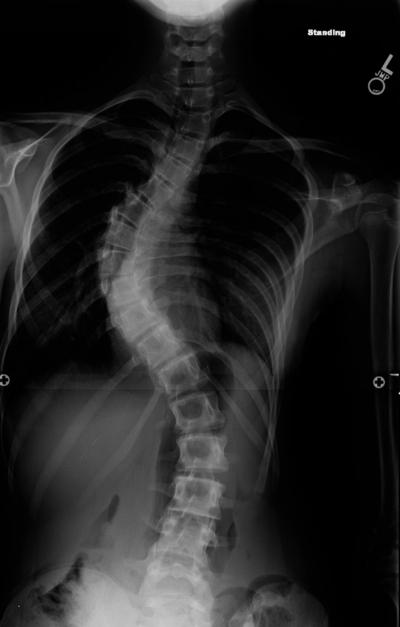

Children with rare mutations in two genes are about four times more likely to develop severe scoliosis than their peers with normal versions of the genes, scientists have found. The research at Washington University School of Medicine in St. Louis has identified genetic risk factors that predispose children to develop s-shaped curves in their spines that are dramatic enough to require surgery.

One to 3 percent of the general population has some mild curvature of the spine. In about one in 10,000 children, scoliosis will produce curvature so pronounced that it requires corrective surgery.